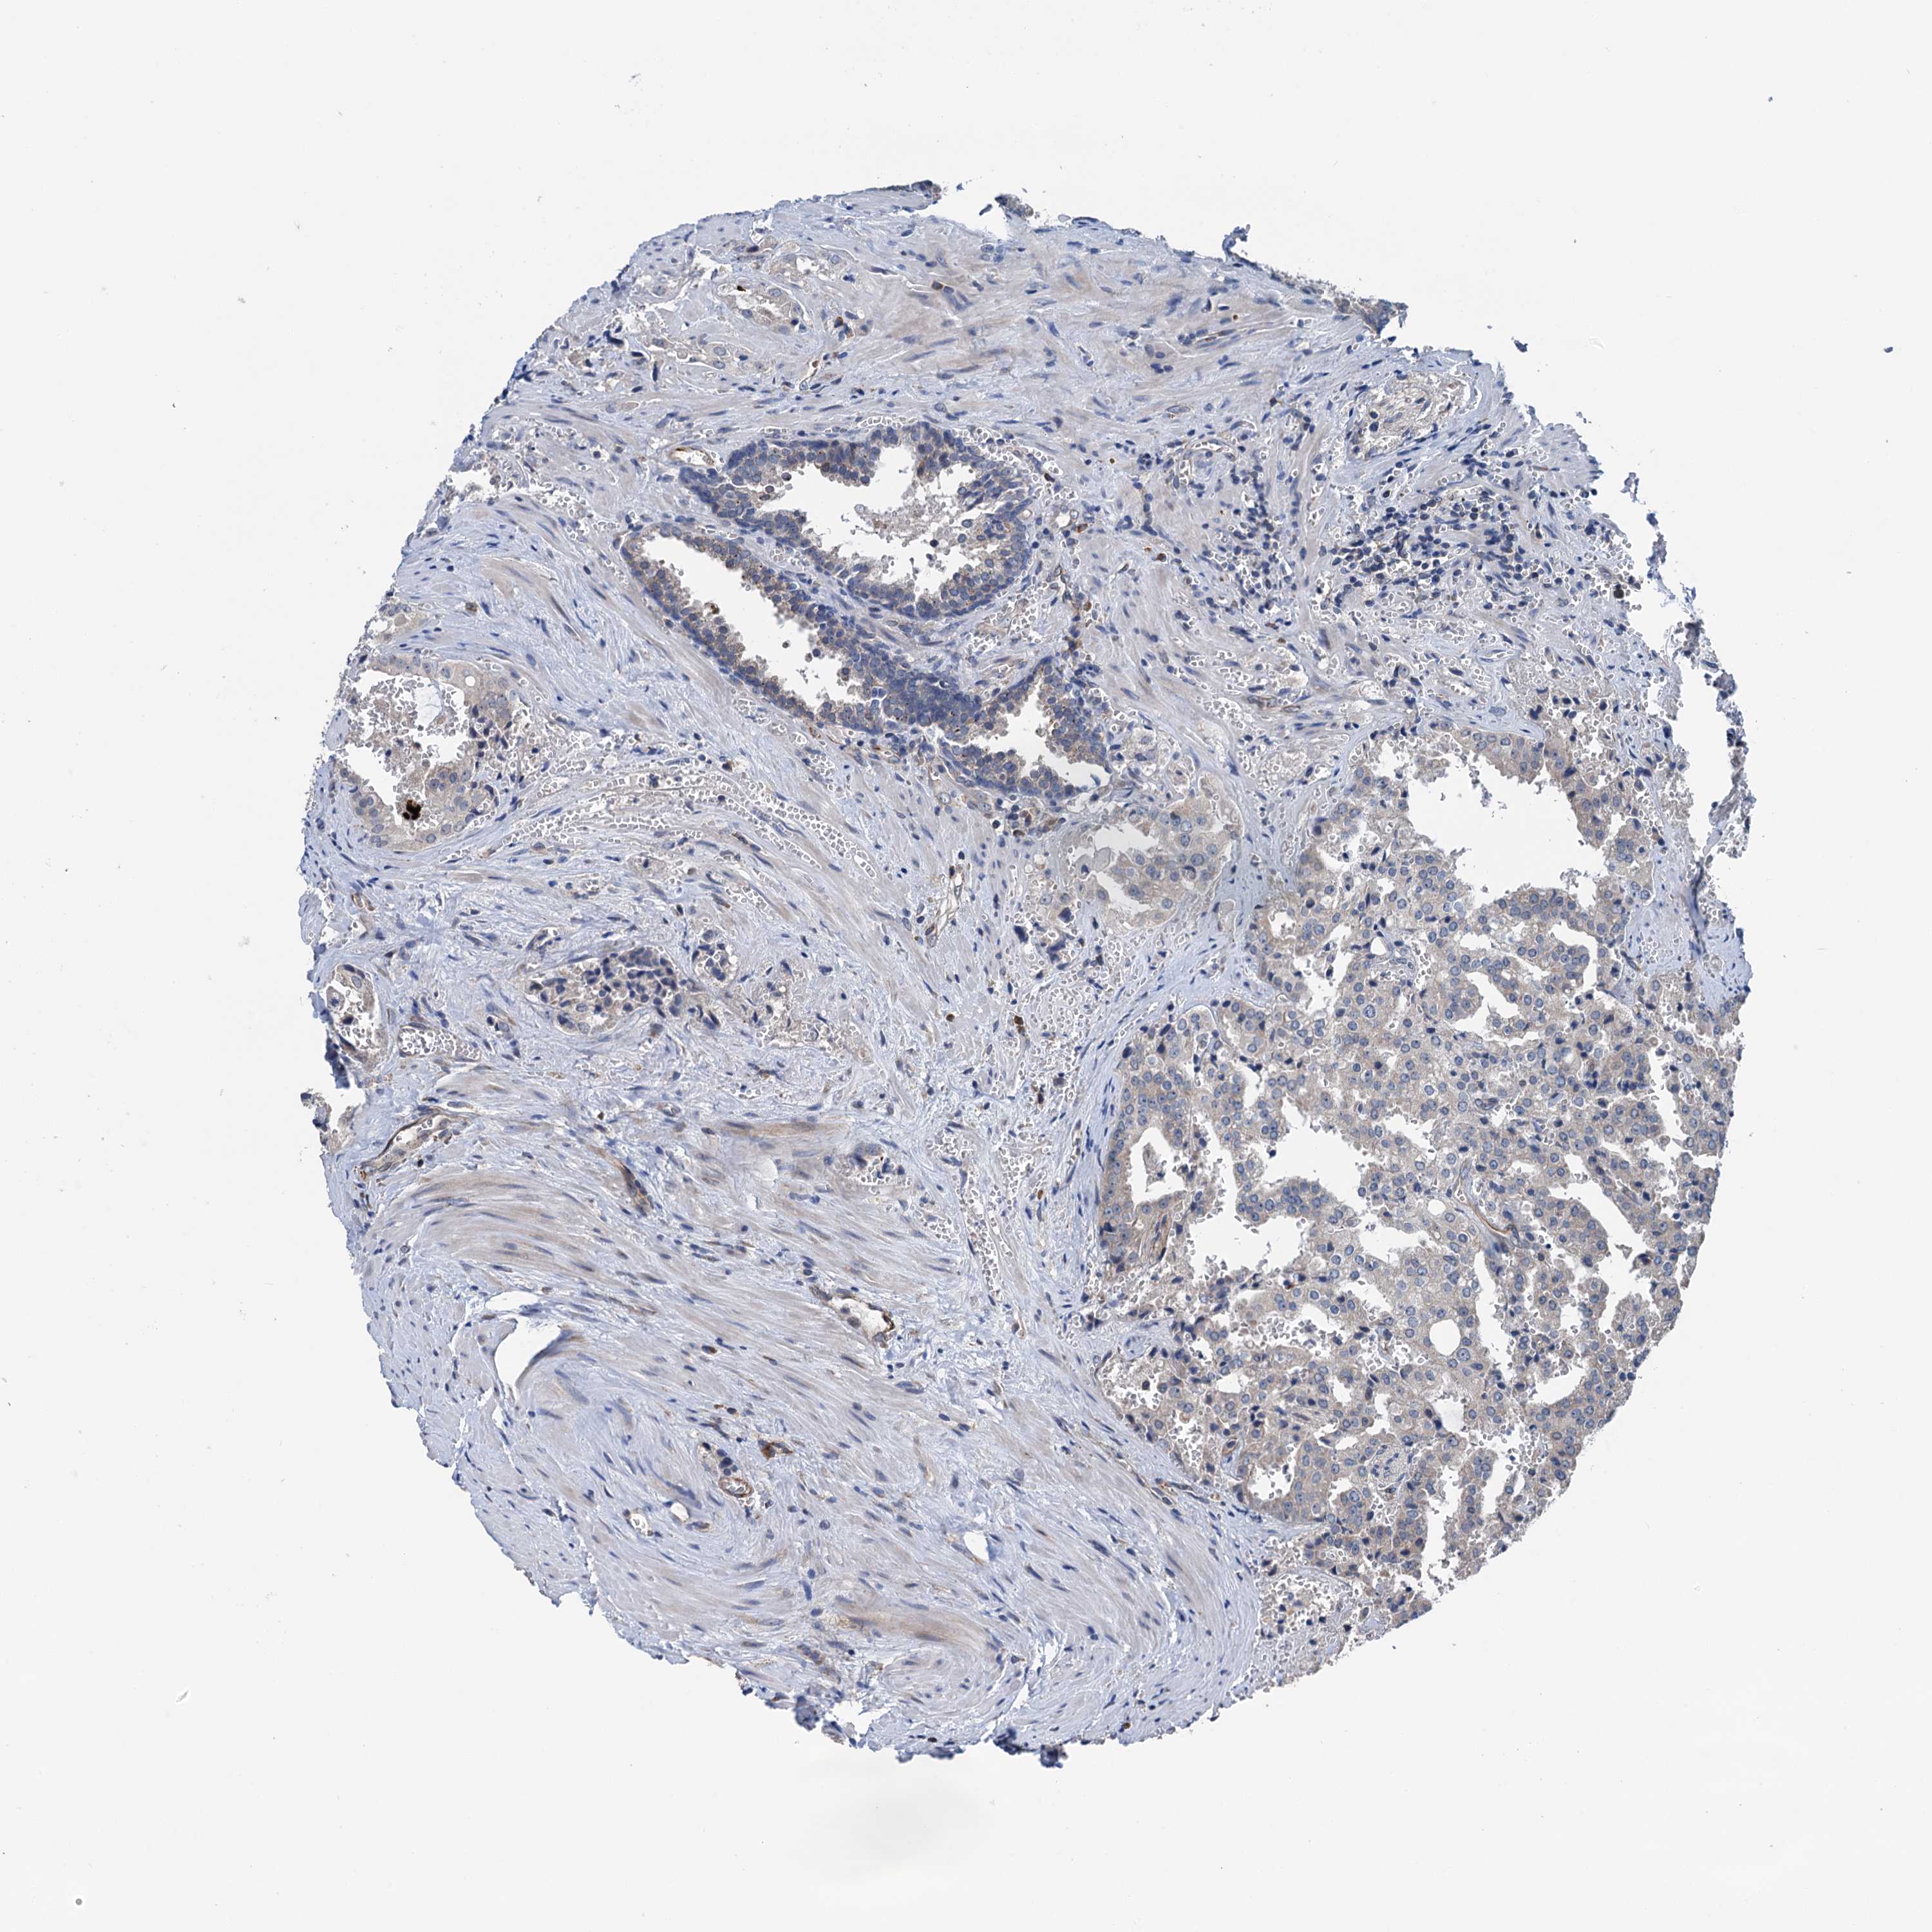

PROSTATE CANCER - Protein expressioni

A mouse-over function shows sample information and annotation data. Click on an image to view it in a full screen mode. Samples can be filtered based on level of antibody staining by selecting one or several of the following categories: high, medium, low and not detected. The assay and annotation is described here.

Note that samples used for immunohistochemistry by the Human Protein Atlas do not correspond to samples in the TCGA dataset.

Antibody stainingi

Antibody staining in the annotated cell types in the current human tissue is reported as not detected, low, medium, or high, based on conventional immunohistochemistry profiling in selected tissues. This score is based on the combination of the staining intensity and fraction of stained cells.

Each image is clickable and will lead to virtual microscopy that enables deeper exploration of all samples and also displays staining intensity scores, fraction scores and subcellular localization as well as patient and tissue information for each sample.

Antibody HPA040867

Staining

High

Medium

Low

Not detected

Intensity

Strong

Moderate

Weak

Negative

Quantity

>75%

75%-25%

<25%

None

Location

Nuclear

Cytoplasmic/membranous

Cytoplasmic/membranous,nuclear

Adenocarcinoma, NOS

Adenocarcinoma, High grade

Adenocarcinoma, Low grade